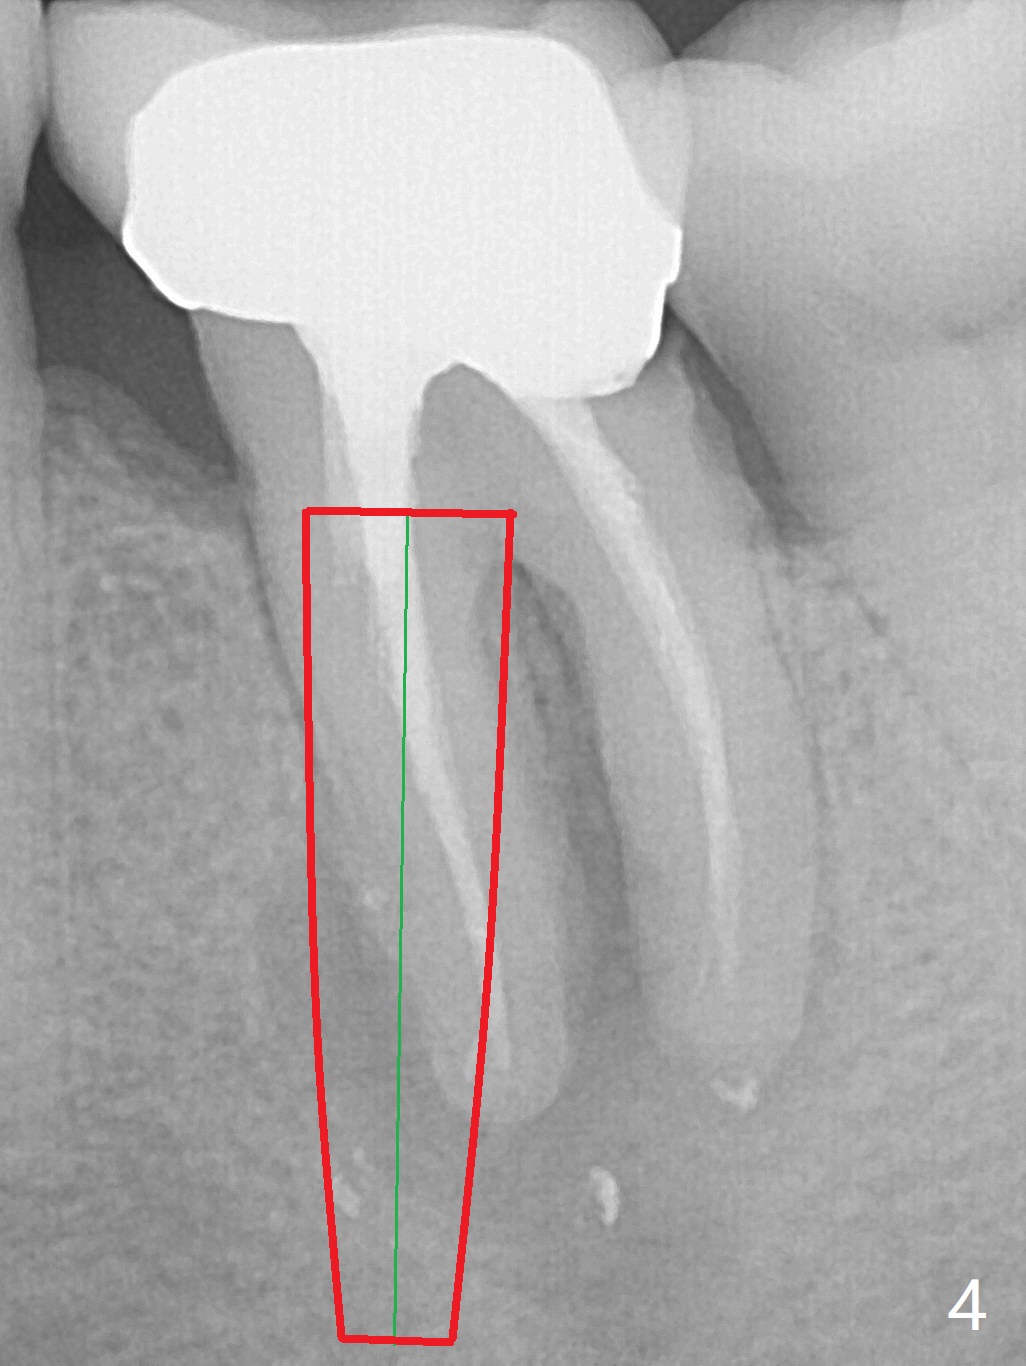

Extraction of the tooth #19 with large PARL (Fig.1,2) confirms the loss of buccal plate, but the crestal bone exists. After failure to place an implant in the middle socket with removal of the lingual septal bone, socket preservation is done with PRF and sticky bone (Fig.3). There is possibility to place a ~4 mm implant in the mesial socket (Fig.4). Or just drop a 5x11 mm Bicon Implant into the large socket, surrounded by sticky bone. When periodontal dressing is removed 18 days postop, the bone graft seems to remain to be "sticky" yellowish, while the granulation tissue has started to grow into the center of the socket from the previously buccal and lingual furcae (Fig.5 reddish). Granulation tissue seems to cover the bone graft (Fig.6), although there is smells when the periodontal dressing is removed. Bone height reduces nearly 3 months postop (Fig.7). The buccal plate collapses (Fig.8), but there seems no further bone loss 4 months postop (Fig.9). Because of buccal plate loss, an implant will be placed lingually with guide (Fig.10-12 green). Bone graft may be placed buccally after implant placement with probing.